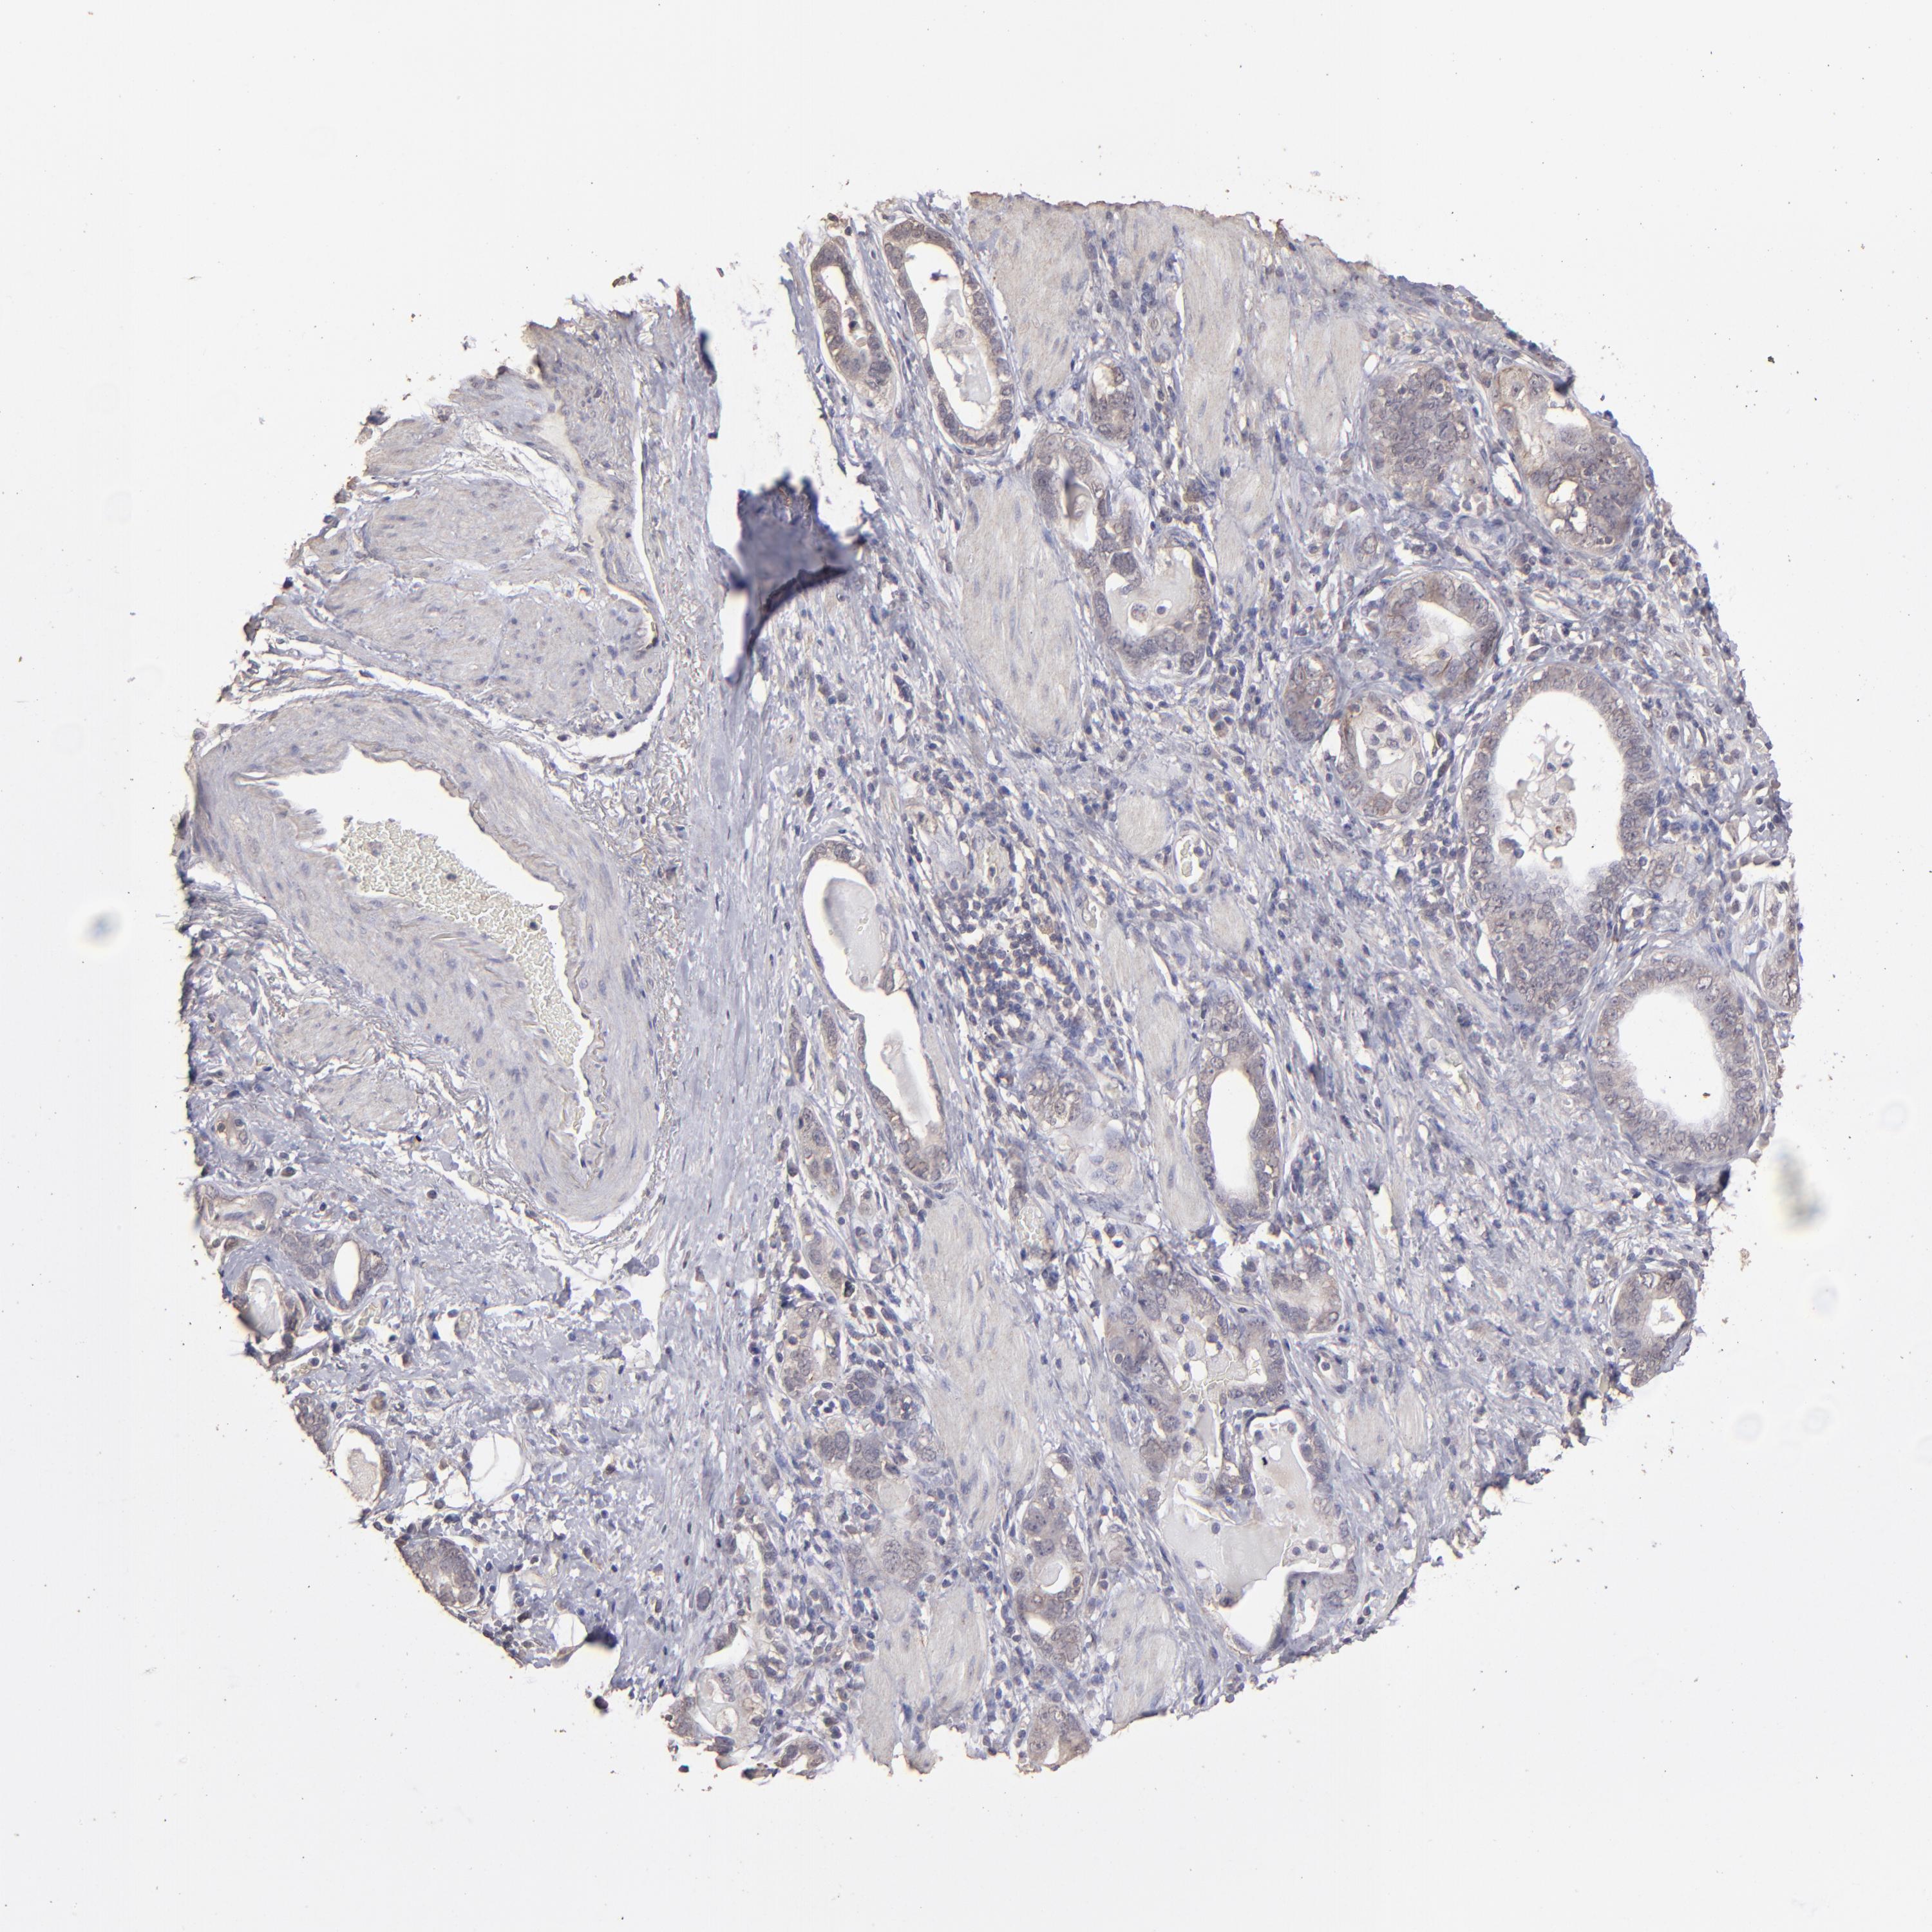

STOMACH CANCER - Protein expressioni

A mouse-over function shows sample information and annotation data. Click on an image to view it in a full screen mode. Samples can be filtered based on level of antibody staining by selecting one or several of the following categories: high, medium, low and not detected. The assay and annotation is described here.

Antibody stainingi

Antibody staining in the annotated cell types in the current human tissue is reported as not detected, low, medium, or high, based on conventional immunohistochemistry profiling in selected tissues. This score is based on the combination of the staining intensity and fraction of stained cells.

Each image is clickable and will lead to virtual microscopy that enables deeper exploration of all samples and also displays staining intensity scores, fraction scores and subcellular localization as well as patient and tissue information for each sample.

Antibody HPA001869

Antibody HPA023882

Adenocarcinoma, NOS

Adenocarcinoma, High grade